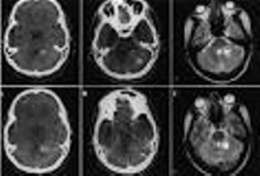

Mutismo acinético. Es un trastorno del comportamiento, caracterizado por la incapacidad para moverse o hablar en pacientes despiertos. Típicamente ha sido descrito como una complicación transitoria de la cirugía de tumores de fosa posterior.

Este síndrome ha sido descrito en la literatura en casos de hidrocefalia con múltiples revisiones valvulares, sin relación con una malfunción valvular. En estos caso, los cambios de volumen ventricular repetitivos afectan a las vías monoaminérgicas ascendentes paraventriculares. Este mecanismo fisiopatológico explicaría la buena respuesta obtenida en algunos casos con el tratamiento con análogos monoaminérgicos, que contrasta con la ausencia de mejoría con las revisiones valvulares.

También puede aparecer como complicación de la cirugía de fosa posterior, pero con una fisiopatología que parece ser diferente. En diferentes series se ha descrito que las lesiones del núcleo dentado o de sus conexiones (las cuales no son preferentemente monoaminérgicas) podrían desencadenar la enfermedad.